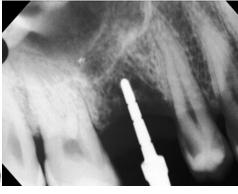

Figura 3. Protocolo de fresado quirúrgico: a) fresa piloto sentido horario, b) comprobación radiográfica, c) RX pin de paralelismo, d) fresa 2.3 sentido antihorario, e) comprobación radiografía periapical de posición y elevación del piso de seno, f) fresa 3.2 a 9mm con elevación evidente, g) verificación de profundidad con sonda del kit de implantes, h) colocación de injerto de hueso NovaBone, i) vista del hueso en el lecho quirúrgico j) fresa final diámetro 4.3, k) RX de comprobación de fresa 4.3 y l) RX de implante e injerto colocados.

fresado (fresa de 4.2 mm de diámetro) dentro del sitio preparado como indica el protocolo de fresado Versah. Gracias al diseño específico de las fresas, el biomaterial fue distribuido hacia las zonas superior y lateral del sitio quirúrgico para promover una adecuada condensación ósea y facilitar la colocación del implante en una posición subcrestal de 1 mm.

Entre cada cambio de fresa, se verificó radiográficamente la dirección y profundidad del fresado. Finalmente, se completó el protocolo con el uso de la fresa de 4.2 mm de diámetro hasta alcanzar una profundidad final de 9 mm. Se obtuvieron imágenes radiográficas que evidencian la correcta colocación del injerto en la elevación lograda (ver Figura 3).

correspondiente, se evaluó la estabilidad primaria mediante la técnica de torque de inserción y una llave dinamométrica, instrumento diseñado para medir y controlar la fuerza aplicada durante la inserción del implante. Este parámetro refleja la resistencia y rigidez de la interfase hueso-implante: a mayor torque, mayor estabilidad primaria (Figura 4).

Figura 4. Comprobación de estabilidad inicial mediante torque de inserción: a) llave dinamométrica inserta el implante a su sitio final y b) acercamiento muestra torque de inserción de 100 N·cm.